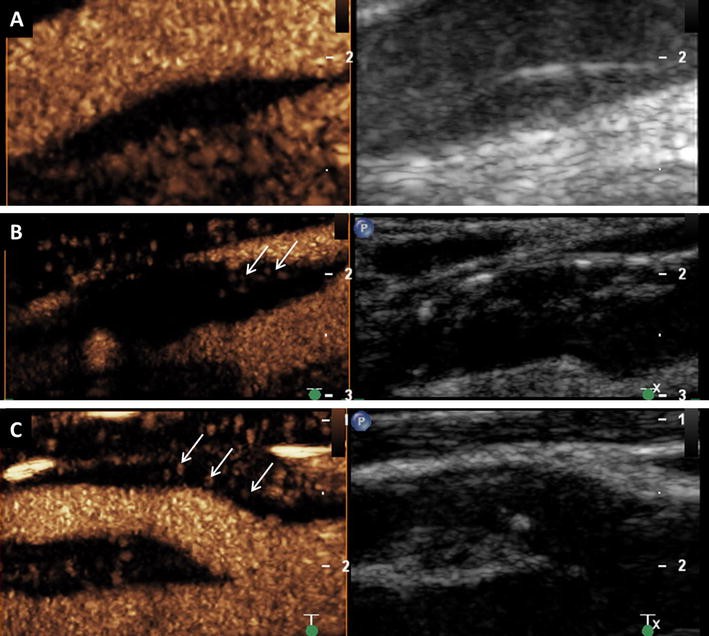

Endoleak after endovascular aortic aneurysm repair on CEUS imaging. a Typ 2 endoleak with enhancement of the aneurysm sac (arrow) caused by retrograde flow form a lumbar artery on CEUS imaging (left side) and corresponding B-mode ultrasound (right side). b Typ 1 endoleak with enhancement of the aneurysm sac (arrow) by an incomplete seal at the proximal end of the graft (main body) on CEUS imaging (left side) and corresponding B-mode ultrasound (right side)

Due to the strictly intravascular distribution and resonance pattern of the contrast agent, CEUS can also be used for detection of endoleaks that are difficult or even impossible to be displayed by CTA due to low flow rates. In one study, CEUS was used additionally in a small number of patients that did not show any signs of endoleak or endograft irregularities during CTA despite increase in aneurysm diameter after EVAR and surprisingly revealed in 100 % of the participants an endoleak and helped to classify it correctly in 80 % of the cases. Results were confirmed by a final subtraction angiography and led to the conclusion that in the event of an unclear aneurysm enlargement after EVAR, CEUS represents a promising diagnostic tool [67]. In addition, CEUS can also be used intraoperatively for early detection of endoleaks or to find appropriate landing zones during EVAR and so important information can be collected to carry out immediately a correction of the stent position during the intervention [68, 69].

Another application in the field of CEUS for endoleak detection, especially to differentiate those with variable flow rates, is the by contrast harmonic imaging optimized perfusion analysis [70]. Hereby, reperfusion of abdominal aneurysm sac after EVAR is determined by a time intensity curve, which, in turn, is derived from bolus administration of contrast agent.